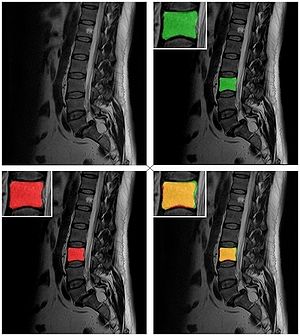

MRI with labeled structures from atlas registered to the CBCT. Registration was carried out with the open source imaging tool 3D Slicer, Version 4.4.0. |